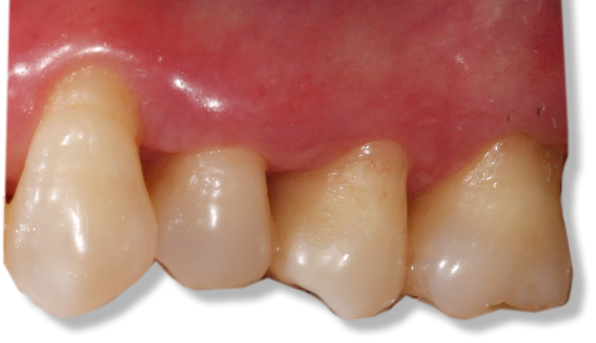

Before and after Periodontal Therapy

![]() | ![]() |

| Untreated severe gum disease | Gum disease treated and stabilised by Dr Halai |